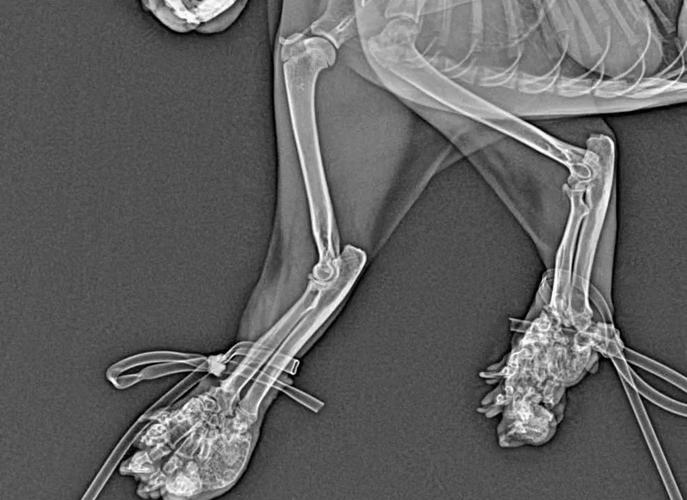

猫软骨病,也被称为猫骨软化症或猫骨质疏松症,是一种影响猫咪骨骼健康的疾病。这种病症主要是由于猫咪体内钙、磷等矿物质代谢异常,导致骨骼变得脆弱、易碎。以下是猫软骨病的一些主要症状:骨骼变形:患有软骨病的猫咪,其骨骼可能会因为矿物质的流失而变得脆弱,进而出现变形。特别是长骨,如股骨和胫骨,可能会变得弯曲或扭曲。

猫咪软骨病是一种由于遗传因素导致的软骨异常疾病,主要见于折耳猫。具体解释如下:病因:折耳猫的遗传性状传递的软骨异常,会导致它们的骨软骨发育不良,进而引发连锁的关节病。症状:最初患腿会变短并出现畸形,生长板异常,关节间隙变窄,新骨形成。

引起猫咪软骨病的主要原因是钙磷比例失调导致的,猫咪缺乏维生素D、缺乏光照等也会直接或间接影响钙磷代谢。猫软骨病的主要症状表现为跛行,建议主人带猫咪去医院进行X光检查,及早治疗。猫软骨病病因 猫咪平时吃的猫粮中钙磷量不足或钙磷比例失调是导致猫咪患软骨病的重要原因。